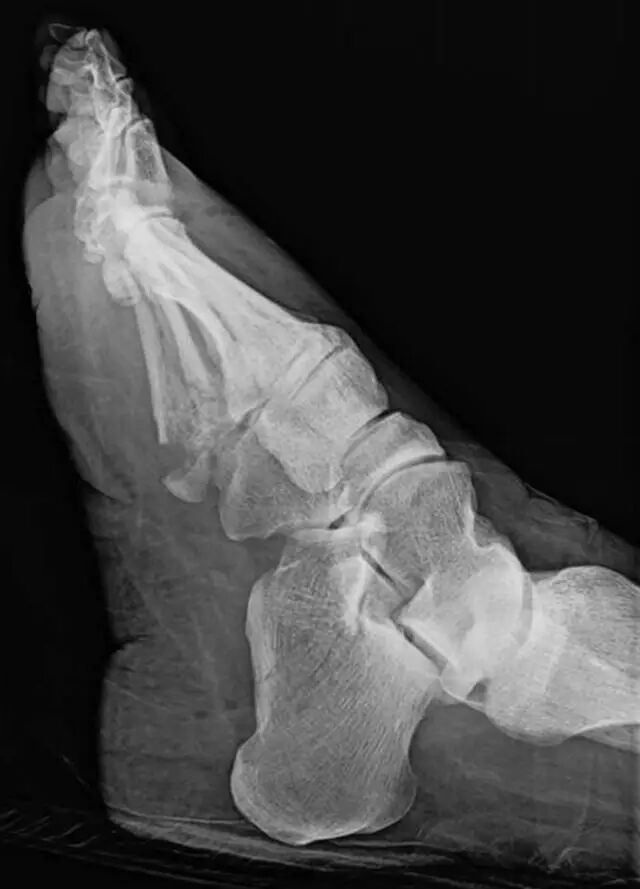

图 9A-61岁的女性在机动车辆碰撞中多发性创伤。多发性骨折脱位导致Satisfaction of SearchA,初步评价足前侧倾斜(A)和侧向(B)足部X线照片对多发跖骨和足趾骨折和多发跖趾关节脱位。最初忽略了跟骨骨折。

怎么取放射片研究--浅析下肢创伤中容易漏诊的X线片_https://www.jmylbn.com_新闻资讯_第24张

图9B-61岁的女性在机动车辆碰撞中持续多发性创伤。多发性骨折脱位导致搜索的满意度。B,初步评价足前侧倾斜(A)和侧向(B)足部X线照片对多发跖骨和足趾骨折以及多发跖趾关节脱位。最初忽略了跟骨骨折。